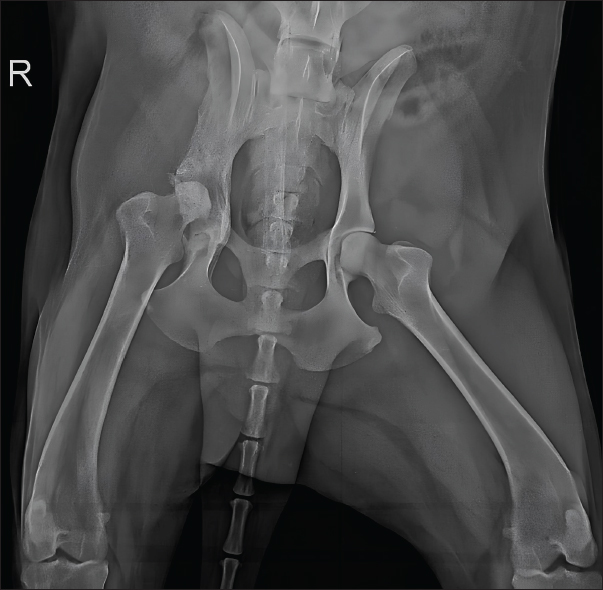

The dog showed significant clinical improvement, including reduced lameness and restored appetite, after 30 days of therapy. Pelvic radiographs revealed slight regression of periosteal proliferation and osteolytic areas (Fig. 4). Hematology and serum biochemistry remained within normal limits.

Fig. 4. Radiographic examination of the dog 30 days after initiation of itraconazole treatment, showing slight regression of periosteal bone proliferation and reduction of osteolytic areas.

Based on clinical and radiographic improvement, itraconazole and gabapentin were continued for an additional 30 days, while cephalexin was discontinued to minimize potential adverse effects. After 60 days of treatment, follow-up radiographs demonstrated continued gradual reduction in osteolysis (Fig. 5). Therapy was extended for an additional 3 months, with ongoing clinical improvement.

Fig. 5. Radiographic examination of the dog 60 days after initiation of itraconazole treatment, showing ongoing, albeit slight, reduction of osteolytic areas.